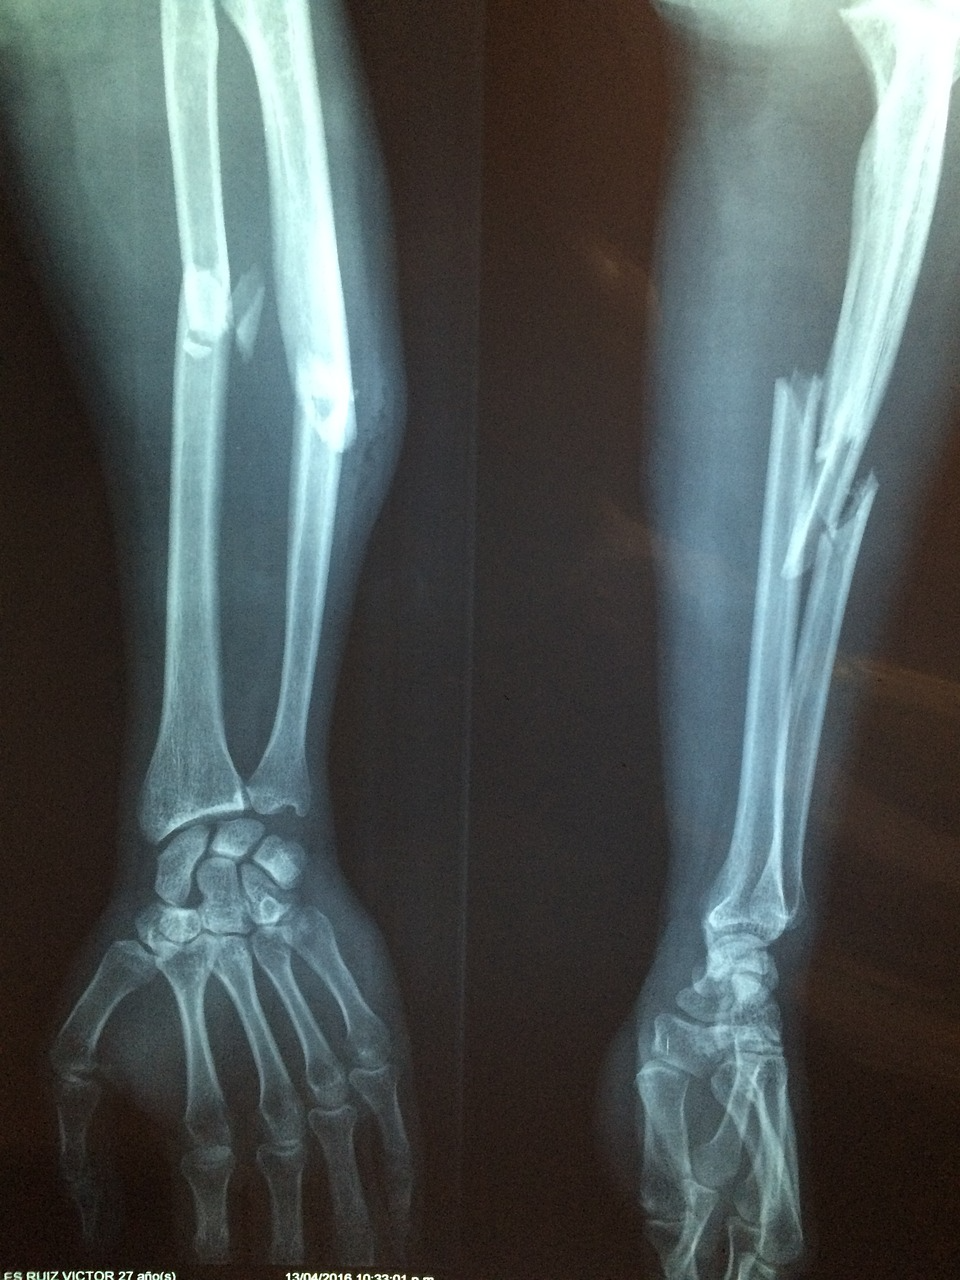

골절은 뼈가 부러지거나 갈라진 상태를 의미합니다. 골절은 단순한 외부 충격이나 사고, 혹은 반복적인 과도한 힘으로 인해 발생할 수 있습니다. 골절은 크게 폐쇄골절(뼈가 피부 밖으로 나가지 않은 상태)과 개방골절(뼈가 피부를 뚫고 밖으로 나온 상태)로 나눠집니다. 골절은 그 위치나 정도에 따라 치료 방법이 달라지므로 신속하게 대응하는 것이 중요합니다.

변형된 형태: 뼈가 부러지면서 손상된 부위가 변형되어 비정상적인 모양을 보이기도 합니다.

탈구는 반드시 병원에서 치료해야 합니다. 구조대가 도착할 때까지 탈구 부위를 고정하고, 가능한 한 안정적으로 대기해야 합니다. 병원에서는 X-ray를 통해 정확한 상태를 확인하고, 의사가 적절한 방법으로 탈구를 복원합니다.